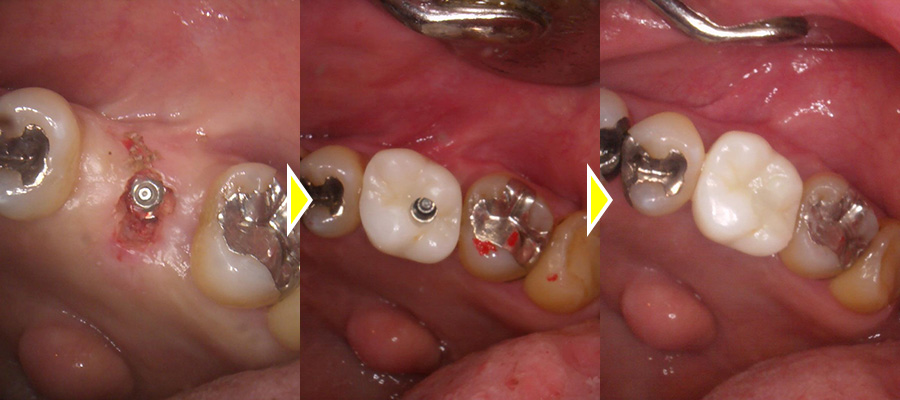

インプラント治療の実施

骨欠損の範囲が大きく、上顎洞までの骨の厚みが3ミリしか無かったため、なるべく長いインプラント体を埋入できた方が安定を得やすいので、上顎洞を挙上させるサイナスリフトも行い、スペースを広げることで骨造成できる範囲も広げ、上顎骨を厚く作り、本来の骨の厚さで予定してたよりも長いインプラント体を埋入することができています。

その後骨造成も併用して口腔内側にも骨を作りました。

上部構造(人工歯)の装着・治療完了

術後は6ヶ月おき、二次オペを行い、骨造成した部位の骨化の確認、骨とインプラント体がしっかりと結合していることが確認できたので、型取りを行い、上部ジルコニアを作成し、セットをしました。

その後は奥歯で硬いものもしっかりと噛むことができるようになり、機能的にも審美的にも満足していただいています。